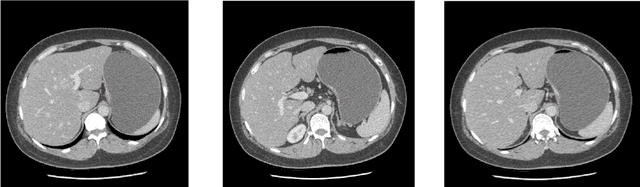

Abstract:Background and Objective: Non-invasively predicting the risk of cancer metastasis before surgery plays an essential role in determining optimal treatment methods for cancer patients (including who can benefit from neoadjuvant chemotherapy). Although developing radiomics based machine learning (ML) models has attracted broad research interest for this purpose, it often faces a challenge of how to build a highly performed and robust ML model using small and imbalanced image datasets. Methods: In this study, we explore a new approach to build an optimal ML model. A retrospective dataset involving abdominal computed tomography (CT) images acquired from 159 patients diagnosed with gastric cancer is assembled. Among them, 121 cases have peritoneal metastasis (PM), while 38 cases do not have PM. A computer-aided detection (CAD) scheme is first applied to segment primary gastric tumor volumes and initially computes 315 image features. Then, two Gradient Boosting Machine (GBM) models embedded with two different feature dimensionality reduction methods, namely, the principal component analysis (PCA) and a random projection algorithm (RPA) and a synthetic minority oversampling technique, are built to predict the risk of the patients having PM. All GBM models are trained and tested using a leave-one-case-out cross-validation method. Results: Results show that the GBM embedded with RPA yielded a significantly higher prediction accuracy (71.2%) than using PCA (65.2%) (p<0.05). Conclusions: The study demonstrated that CT images of the primary gastric tumors contain discriminatory information to predict the risk of PM, and RPA is a promising method to generate optimal feature vector, improving the performance of ML models of medical images.